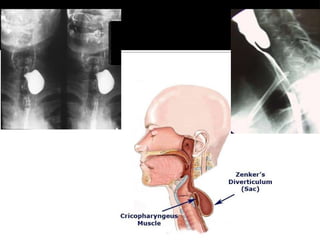

◾ Pharyngeal pouch that develops in the

proximal esophageal wall

◾ Pulsion diverticula involving only the

mucosa

 located between thyropharyngeal and

cricopharyngeus muscle

Diagnosis is based highly on clinical

observations and patient history

Avoid upper endoscopy if known or

highly suspicious due to risk of

rupture

Barium swallow

 confirms diagnosis by visualizing

pharyngeal outpouch